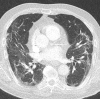

Chest CT has a potential role in the diagnosis, detection of complications, and prognostication of coronavirus disease 2019 (COVID-19). Implementation of appropriate precautionary safety measures, chest CT protocol optimization, and a standardized reporting system based on the pulmonary findings in this disease will enhance the clinical utility of chest CT. However, chest CT examinations may lead to both false-negative and false-positive results. Furthermore, the added value of chest CT in diagnostic decision making is dependent on several dynamic variables, most notably available resources (real-time reverse transcription-polymerase chain reaction [RT-PCR] tests, personal protective equipment, CT scanners, hospital and radiology personnel availability, and isolation room capacity) and the prevalence of both COVID-19 and other diseases with overlapping manifestations at chest CT. Chest CT is valuable to detect both alternative diagnoses and complications of COVID-19 (acute respiratory distress syndrome, pulmonary embolism, and heart failure), while its role for prognostication requires further investigation. The authors describe imaging and managing care of patients with COVID-19, with topics including (a) chest CT protocol, (b) chest CT findings of COVID-19 and its complications, (c) the diagnostic accuracy of chest CT and its role in diagnostic decision making and prognostication, and (d) reporting and communicating chest CT findings. The authors also review other specific topics, including the pathophysiology and clinical manifestations of COVID-19, the World Health Organization case definition, the value of performing RT-PCR tests, and the radiology department and personnel impact related to performing chest CT in COVID-19. ©RSNA, 2020.